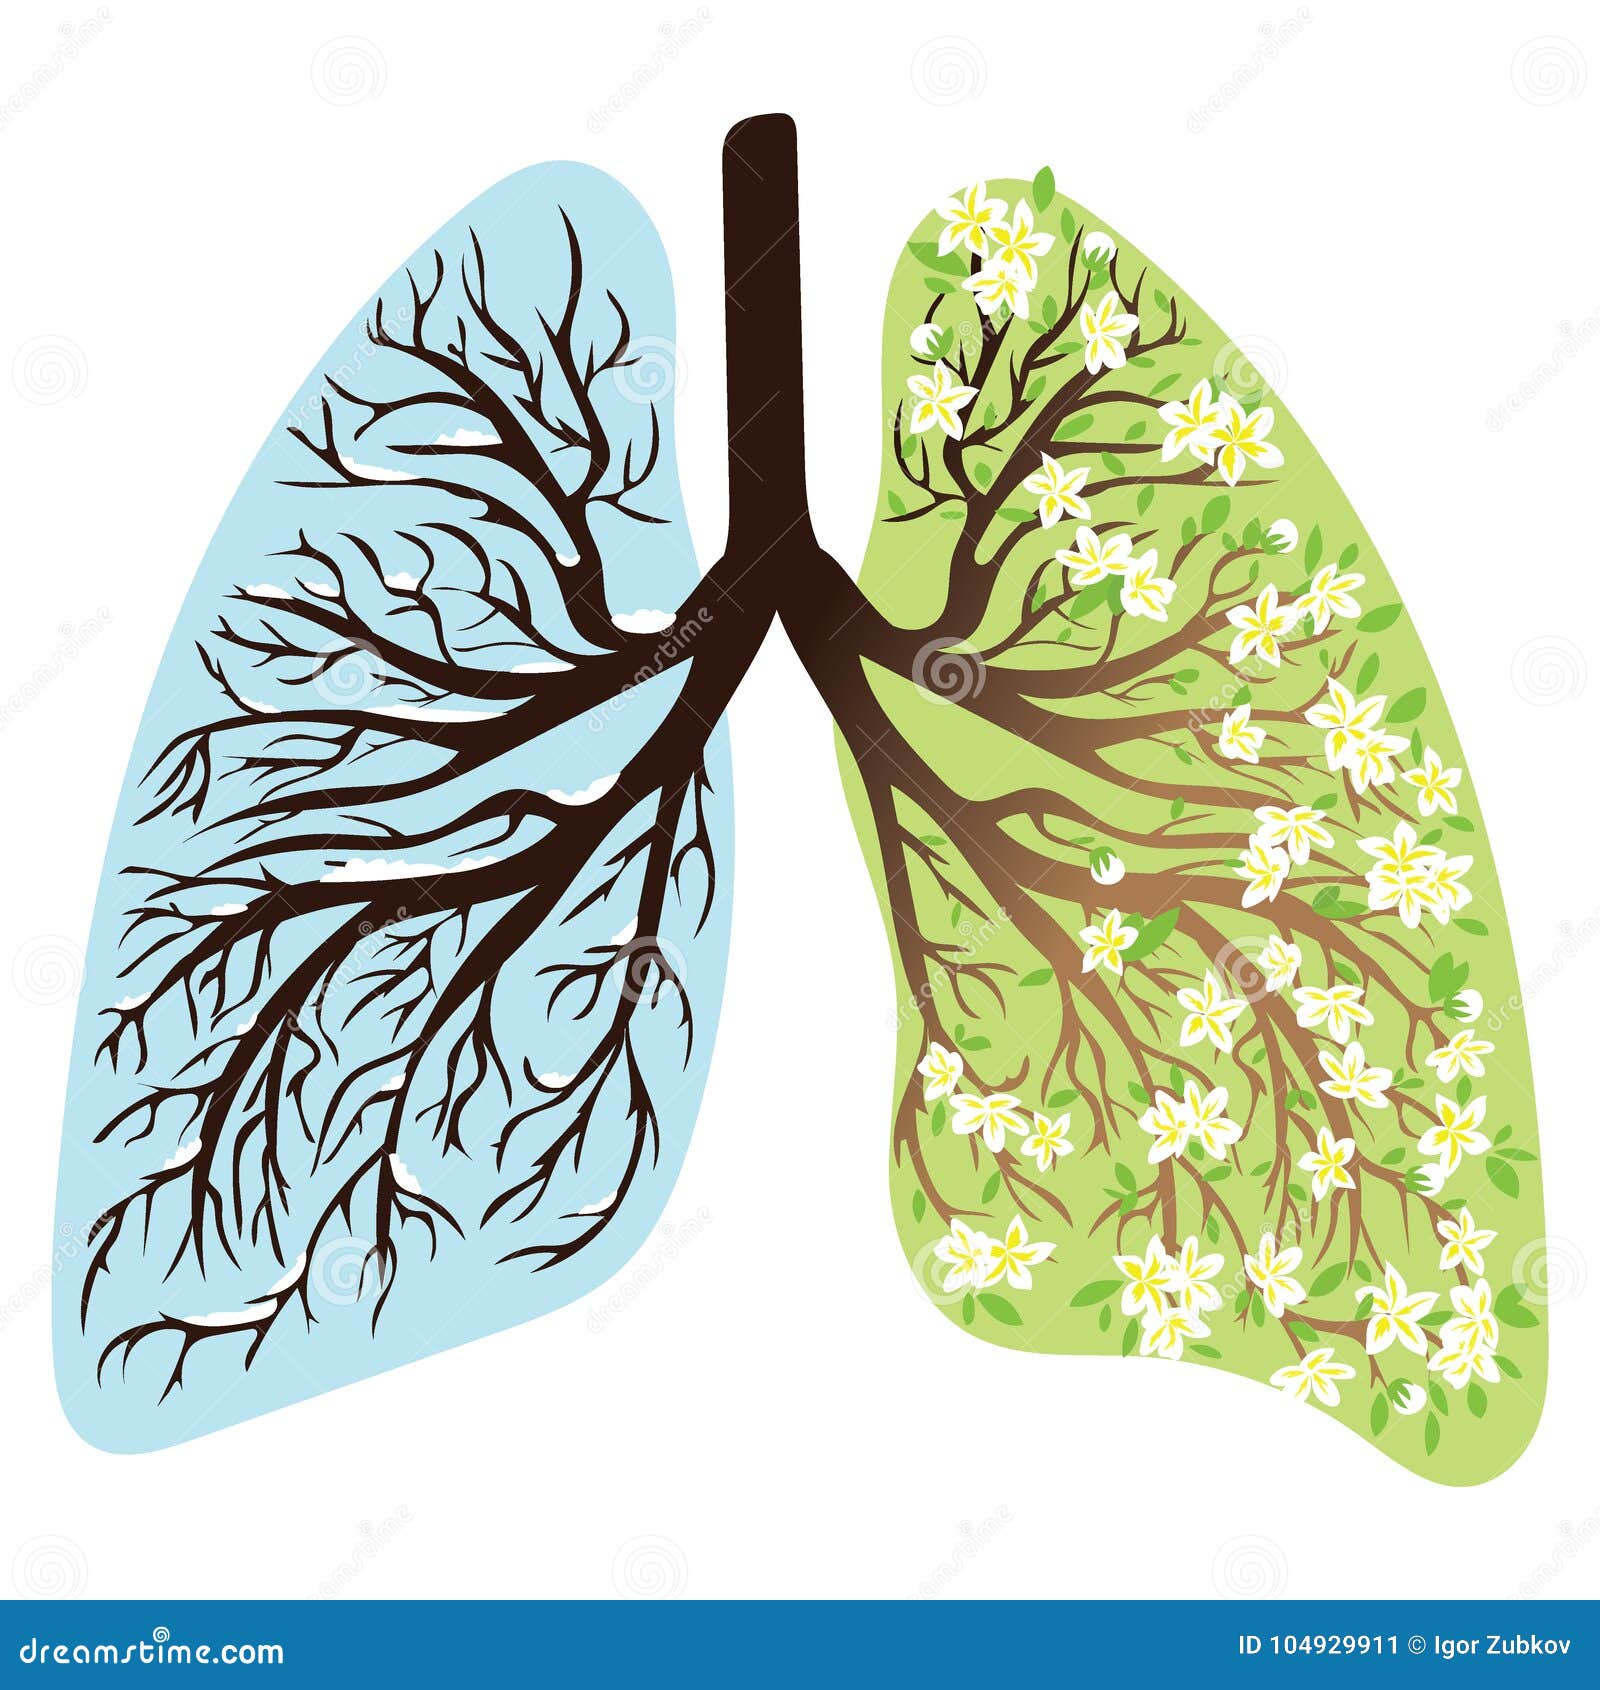

Здоровые Легкие Картинки

Здоровые Легкие Картинки 117 фото